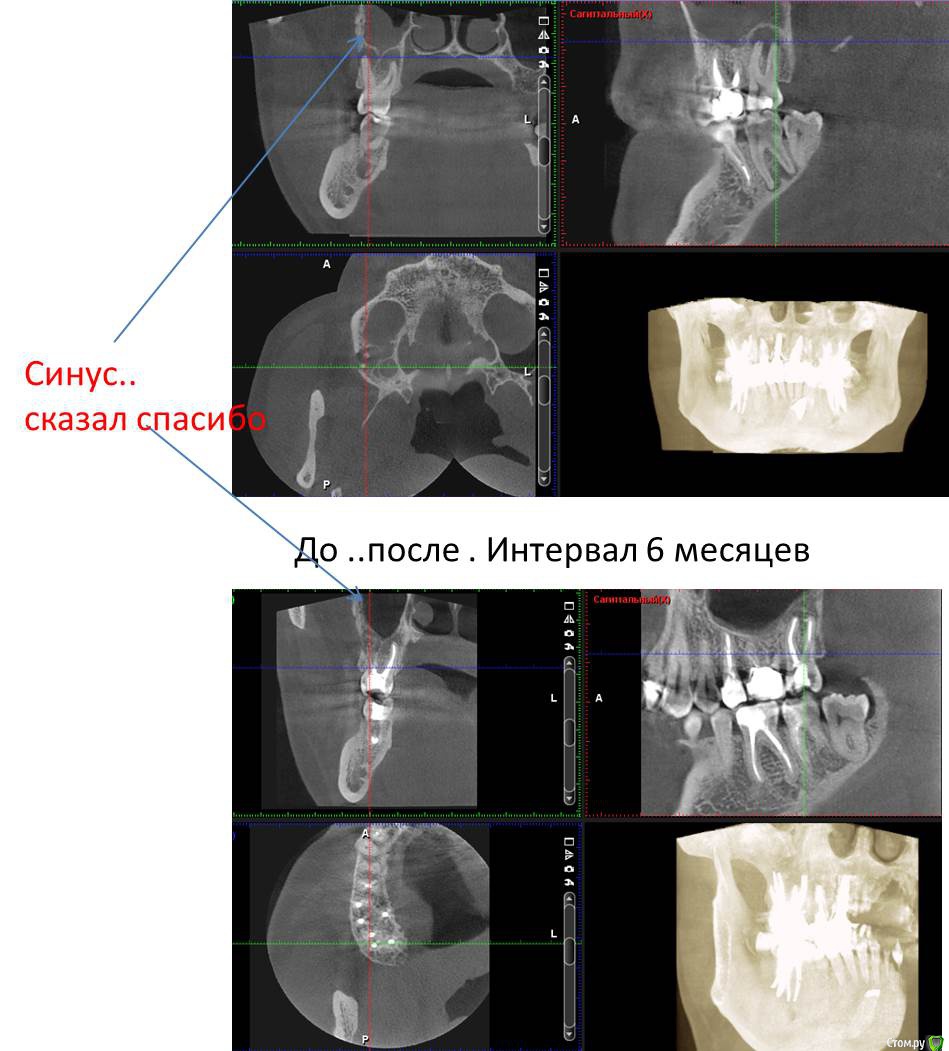

Л Ю С Я Опубликовано 5 декабря, 2016 Поделиться Опубликовано 5 декабря, 2016 Полечили гаиморит без ЛОР. Срок наблюдения 6 месяцев. Теперь на очереди 2.7 5 Ссылка на комментарий

Л Ю С Я Опубликовано 5 декабря, 2016 Поделиться Опубликовано 5 декабря, 2016 КлассДа, очень показательно. Хотя пациентка сначала не верила в успех, поэтому от лечения 2.7 отказалась. 10 лет мучений, не знаю ,почему лор не заподозрил одонтогенный. Пришла начитавшись Интернета про причины гайморита. Видимо не зря читала))) Ссылка на комментарий

Сева северный Опубликовано 5 декабря, 2016 Поделиться Опубликовано 5 декабря, 2016 (изменено) Отлично ... определяющим в вашем случае является клиника. Рентгенологически .. как мне видется, пазуха все еще вовлечена. Изменено 5 декабря, 2016 пользователем Сева северный Ссылка на комментарий

Л Ю С Я Опубликовано 6 декабря, 2016 Поделиться Опубликовано 6 декабря, 2016 Рентгенологически .. как мне видется, пазуха все еще вовлечена.Где? Ссылка на комментарий